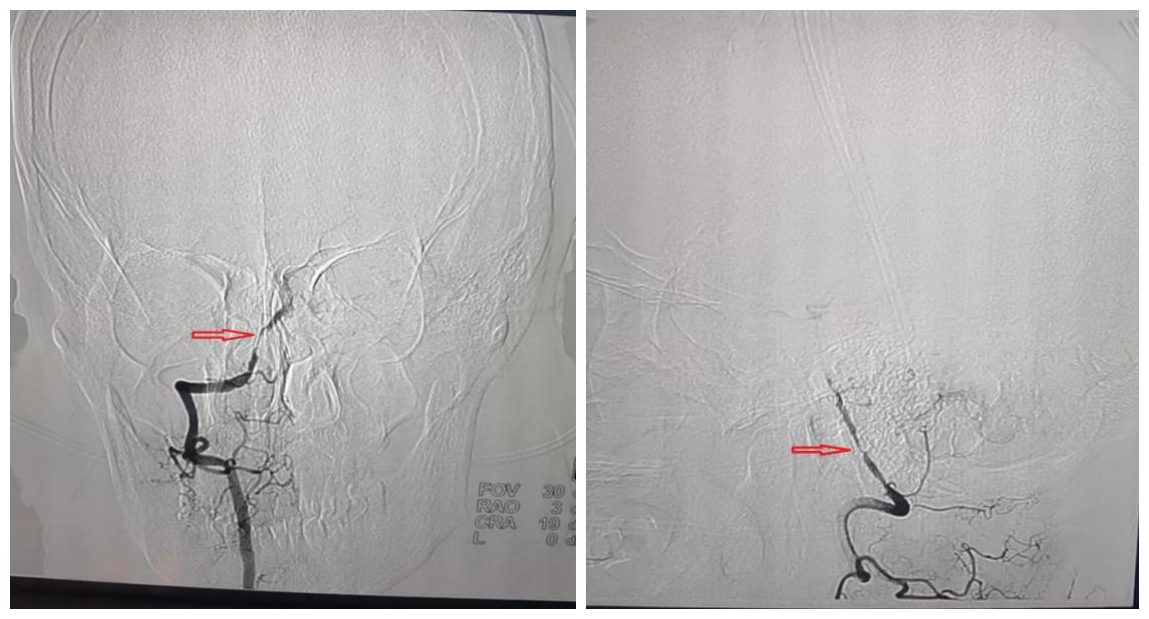

我院造影检查(右侧V4段重度狭窄)

检查结果不出所料,吴先生的右侧椎动脉严重狭窄,正向血流严重减少,这就是导致患者延髓缺血,出现头晕、偏瘫等脑梗死症状的罪魁祸首。由于患者之前没有发生过脑梗症状,发病后尚没有规律服药和控制脑梗的危险因素,综合考虑张院长决定先为吴先生实施药物治疗。两周后吴先生的症状明显好转。